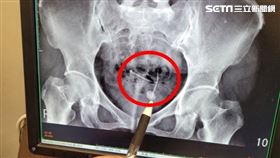

58歲王女士,半年來經常泌尿道感染,而且很容易頻尿,...

2020/10/31 08:14